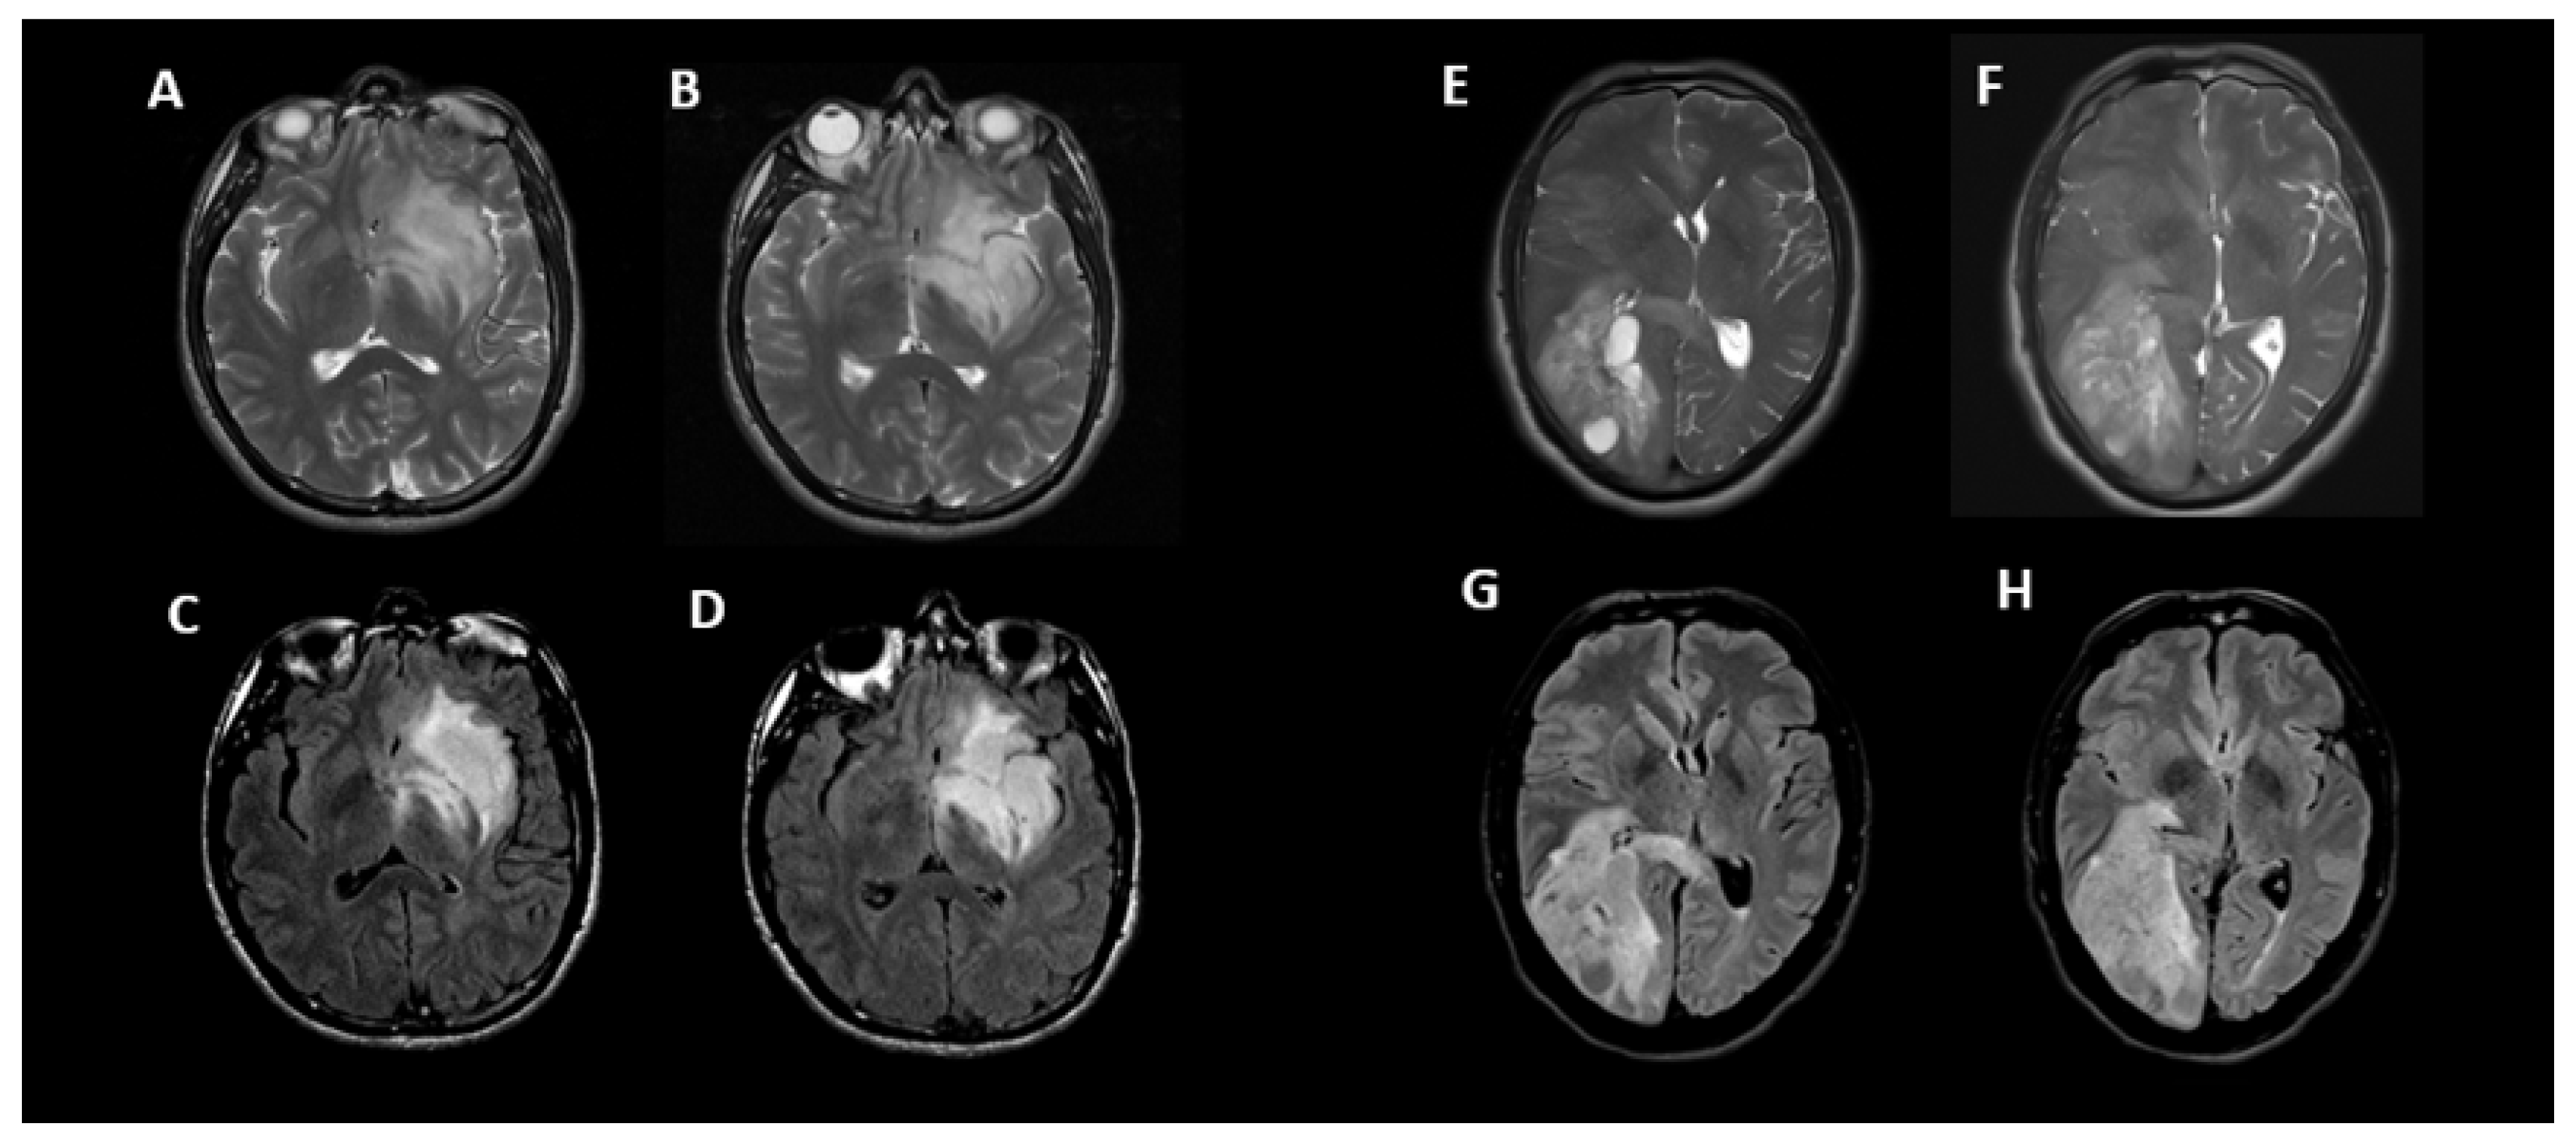

Examples of true positive, true negative, false positive, and false negative results for T2-FLAIR mismatch using consensus reads against 1p/19q co-deletion status are shown in Figure 2.

Figure 2. Examples of T2-FLAIR match and mismatch in 4 patients with IDH1 mutant gliomas with various 1p/19q co-deletion status. Axial T2 (A) and FLAIR (B) images demonstrate T2-FLAIR mismatch in a 25-year-old male with 1p/19q non-co-deletion correctly identified in a true positive instance. Axial T2 (C) and FLAIR (D) images demonstrate T2-FLAIR mismatch in a 58-year-old female with 1p/19q co-deletion in a false positive instance. Axial T2 (E) and FLAIR (F) images show T2-FLAIR match in a 55-year-old male with 1p/19q non-co-deletion in a false negative instance. Axial T2 (G) and FLAIR (H) images show T2-FLAIR match in a 60-year-old female with 1p/19q non-co-deletion correctly identified in a true negative instance. All cases were correctly identified by radiomic model.